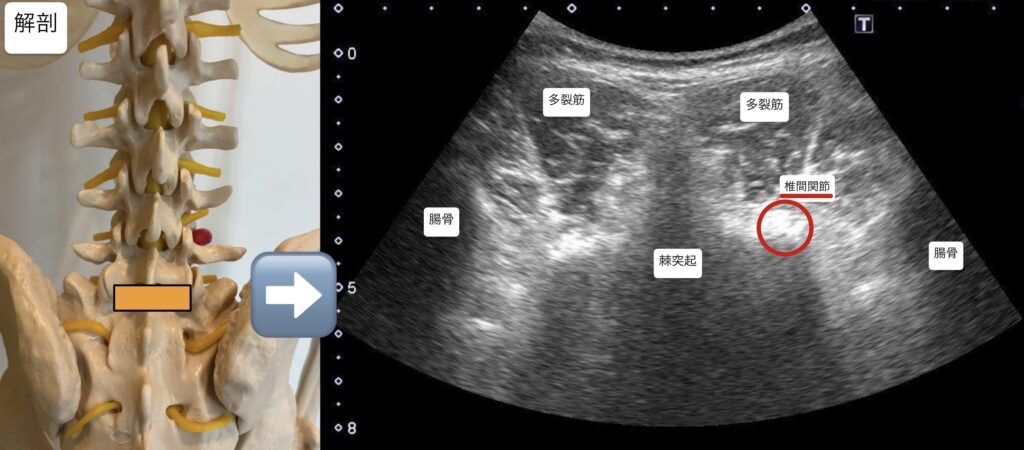

・腰椎5番神経根に対し、超音波エコーガイド下で鍼通電を行った。

腰椎5番神経根に対する施術で運動や筋力が即時改善したことから、神経根周囲の機械的ストレスによって神経周囲の環境悪化、血流低下が出ていたと考える。